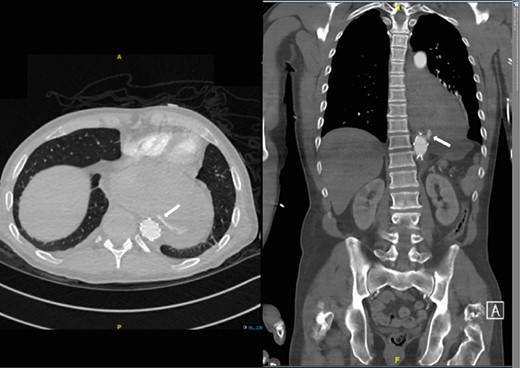

A 57-year-old male presented haemodynamically unstable with a blood pressure of 85/50 mmHg and a heart rate of 136 bpm with haematemesis, melaena and 4-day history of back pain. Fifteen years previously he was treated for a poorly differentiated adenocarcinoma (pT3 pN1 MX) close to the gastro-oesophageal junction with chemotherapy and trans-hiatal oesophagectomy. He received no radiotherapy. Apart from being a life-long smoker he had no other positive social risk factors or medical history. He underwent immediate oesophago-gastro-duodenoscopy (OGD). This showed fresh and clotted blood in the gastric remnant but no bleeding source was identified. He had a pulseless arrest during the OGD but underwent successful cardiopulmonary resuscitation. Following this a CT angiogram was performed. This demonstrated a fistula between the neo-oesphagus and the thoracic aorta (Fig. 1). Following discussion between an upper gastro-intestinal surgeon, a vascular surgeon and an interventional radiologist the patient was taken to the operating theatre. Under general anaesthesia an initial thoracic aortogram was performed from the right groin to confirm the presence and location of the AGF (Fig. 2). Following this, a covered thoracic stent graft (Cook Medical ZTA-24-105/diameter of 24 mm and length of 105 mm), was inserted via the femoral artery under image guidance. The stent graft, usually used in aneurysmal repair, was placed in the thoracic aorta across the fistula and occluded it. Subsequent angiogram showed no leak (Fig. 3). The patient became haemodynamically stable and had an uneventful recovery.

CT angiogram showing aorta-enteric fistula demonstrated by arrow (axial and sagittal view, respectively).

Second admission: CT angiogram showing aorta-enteric fistula demonstrated by arrow (axial and sagittal view, respectively).